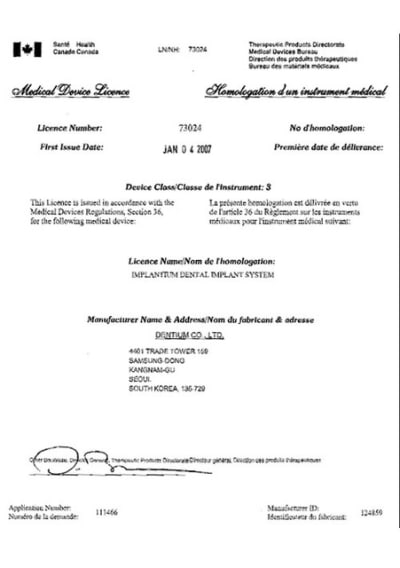

Peut-être que Dentium sera disponible chez moi en 2012.

Apparemment si, même s'il n'y a pas de distributeur local.

le dentium est un implant sympa...mais j'ai du mal avec dès que l'os est dense...sa stab primaire en cas d'os mou est due à sa forme en S, pas au filetage peu agressif et carré et donc peu autotaraudant...ceci explique aussi mes difficultés rencontrées en cas d'os dur car du coup il a du mal, je trouve, à créer son filetage dans l'os...enfin, c'est mon ressenti perso...